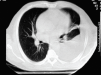

Fig. 1. Derrame pleural izquierdo con atelectasia por comprensión del lóbulo inferior.